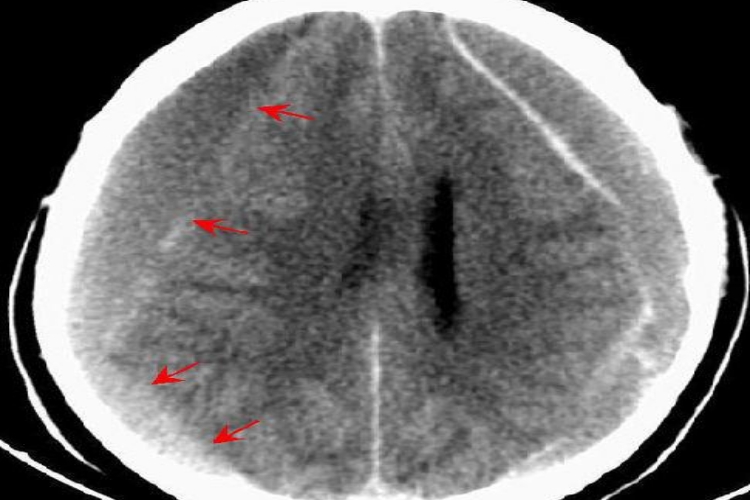

宝宝摔到头侧面鼓软包的症状,主要见于头皮血肿,因血肿发生的层次部位不同,可分为头皮下血肿或骨膜下血肿,两者都表现为头皮侧面局部肿块。

头皮下血肿:头皮下血肿一般体积较小,有时因血肿周围组织肿胀隆起,中央相对凹陷,似凹陷性颅骨骨折。头皮下血肿张力高,压痛明显。

骨膜下血肿:骨膜下血肿的特点是因有颅骨缝的限制,血肿局限于某一颅骨范围之内,以骨缝为界,边缘清楚,张力较高,密度高于软组织。